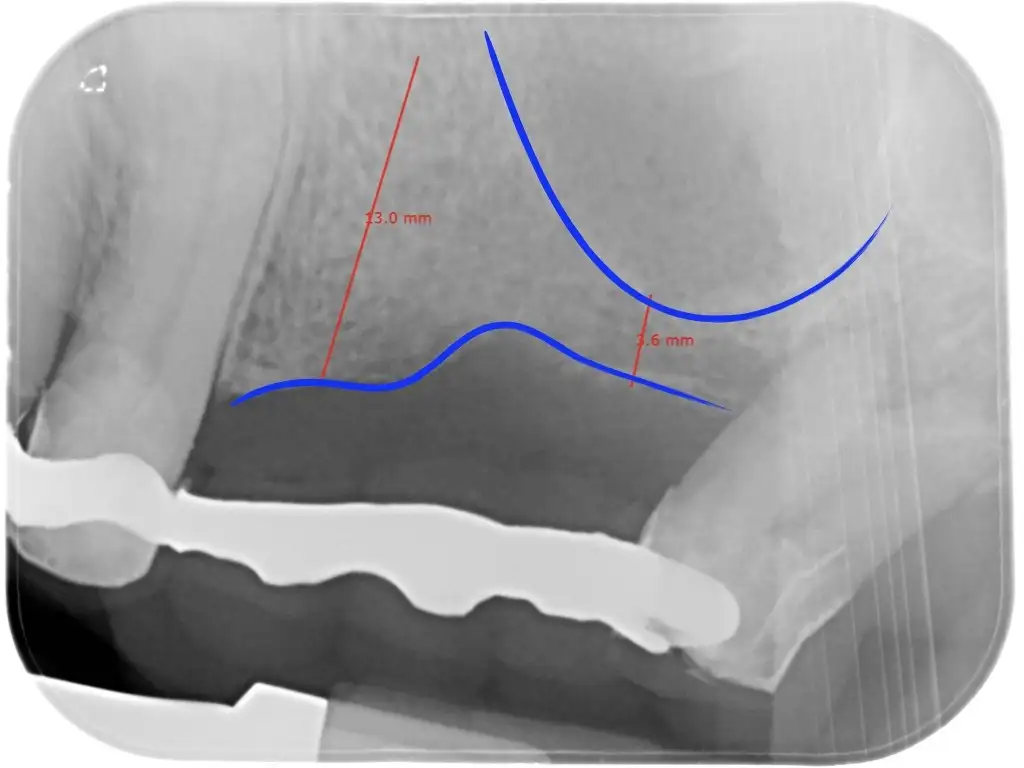

In questi casi si può intervenire sollevando la membrana che copre il pavimento del seno mascellare, inserendo il biomateriale e fissando (nella grande maggioranza dei casi) già l’impianto. Tutto ciò sarà fatto in un unico intervento.

L’accesso al seno mascellare potrà essere dalla parete laterale (grande rialzo) nei casi più complessi o addirittura attraverso il piccolo foro realizzato per posizionare l’impianto in modo ancora più mininvasivo (mini-rialzo).